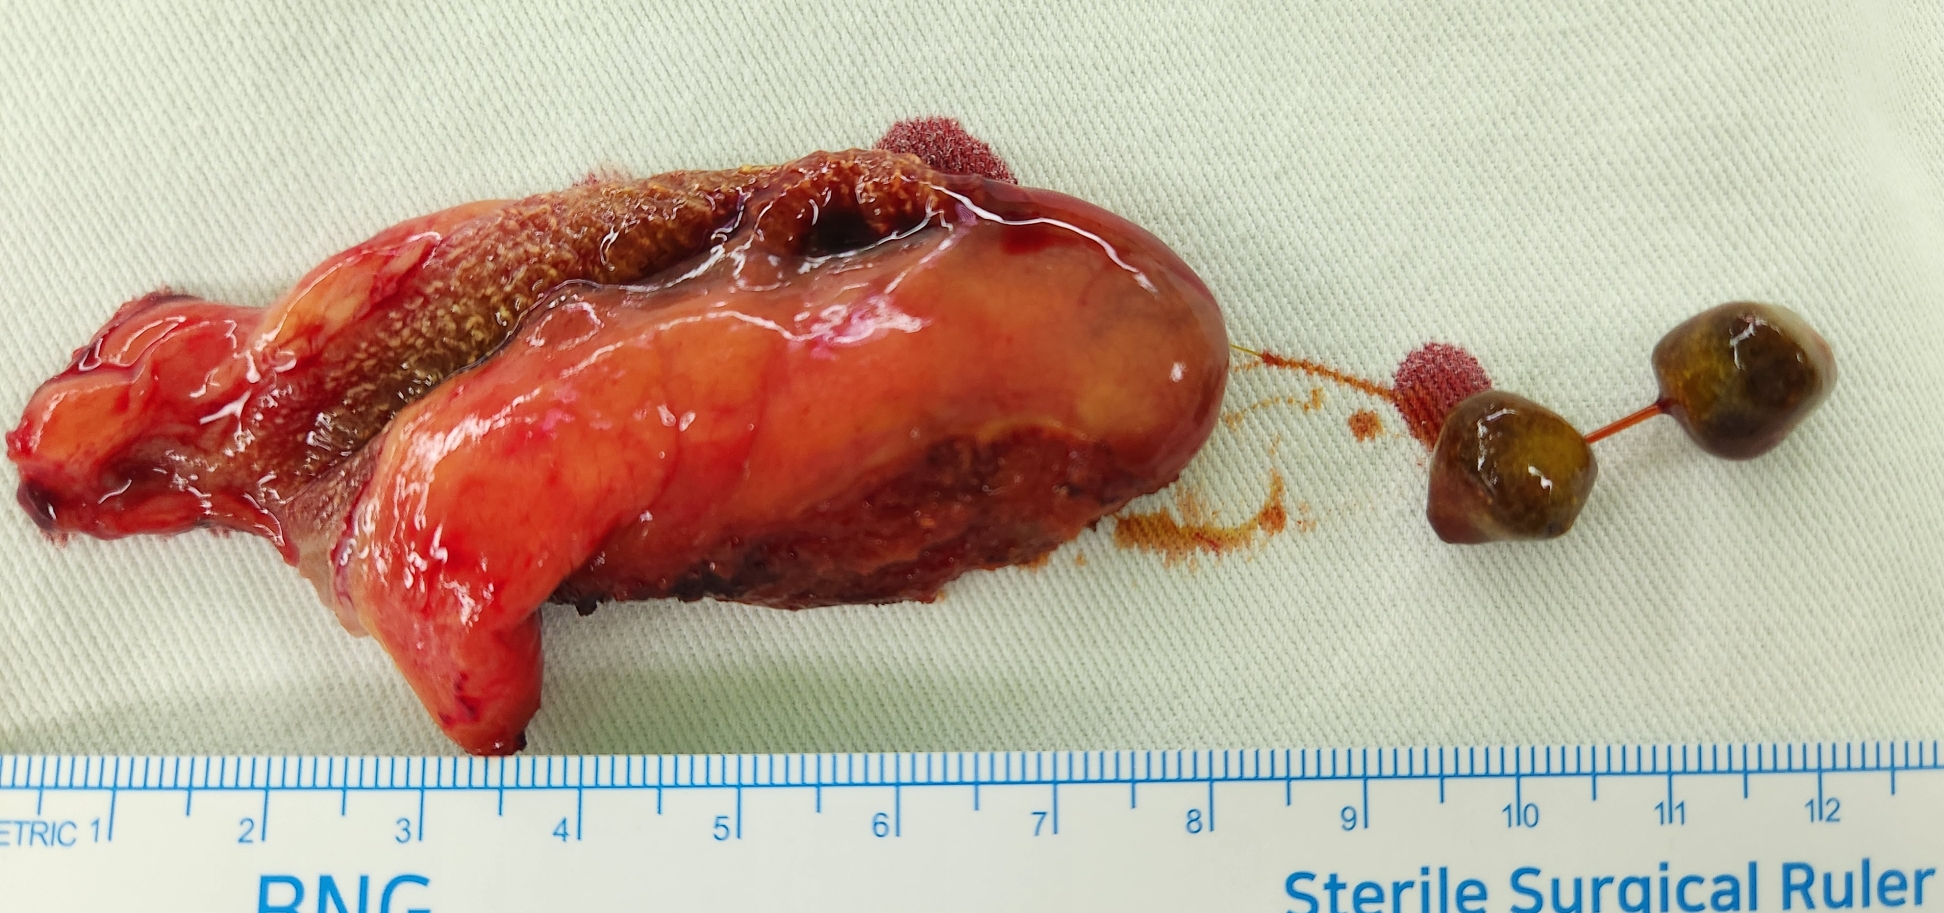

영덕 계시는 분인데 복통으로 영덕 내과병원에서 시행한 초음파상 담석 담낭염이 발견되어 제게 수술을 받으러 오셨던 분입니다.

방금 단일공 복강경 담낭절제술을 시행했습니다.

수술은 30분 걸렸습니다.